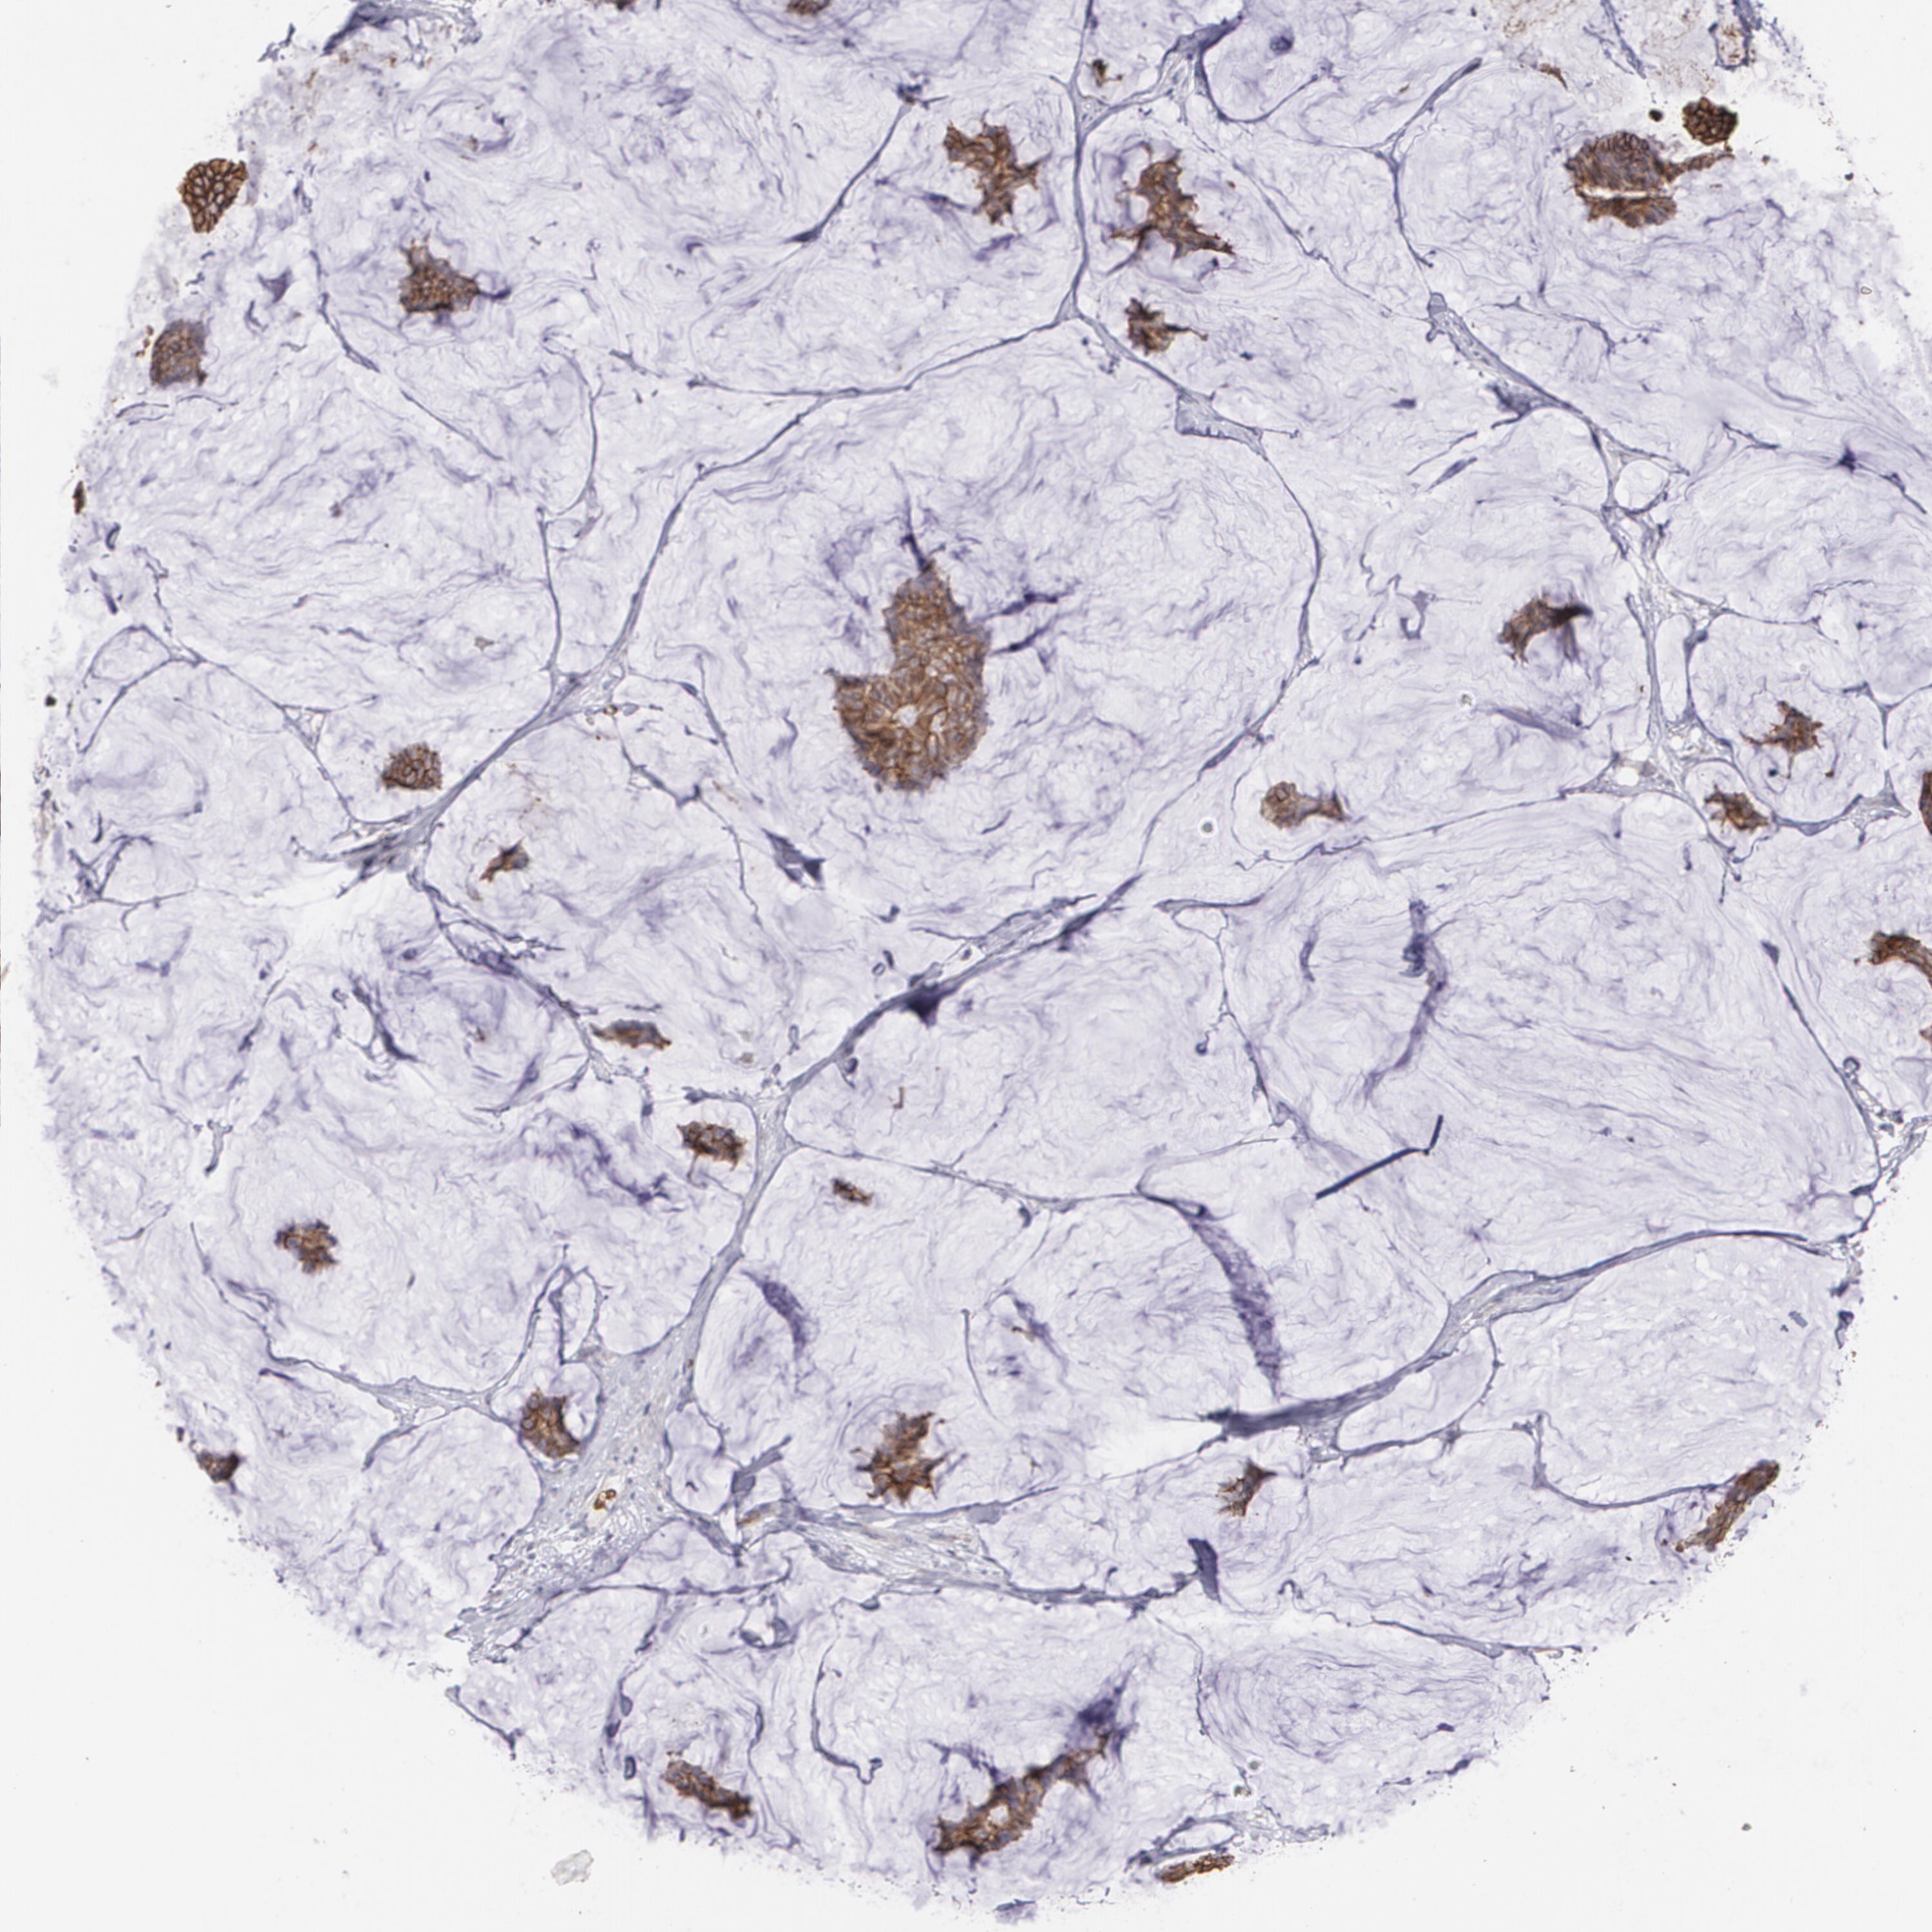

CANCER BREAST CANCER Show tissue menu

BRCA TCGA BRCA VALIDATION PROTEIN EXPRESSION

Breast cancer

Human cancer